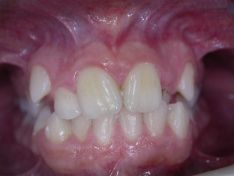

Spesso durante la fase di crescita possiamo notare nei ragazzi un disallineamento dei denti che può essere più o meno severo. In questi casi è possibile intervenire intercettando il problema attraverso una diagnosi corretta e risolverlo con l'utilizzo di un apparecchio ortodontico fisso. In questo caso vediamo una giovane paziente che presentava un grave disallineamento dentale risolto nell'arco di 21 mesi.

Grave affollamento dentale superiore e inferiore